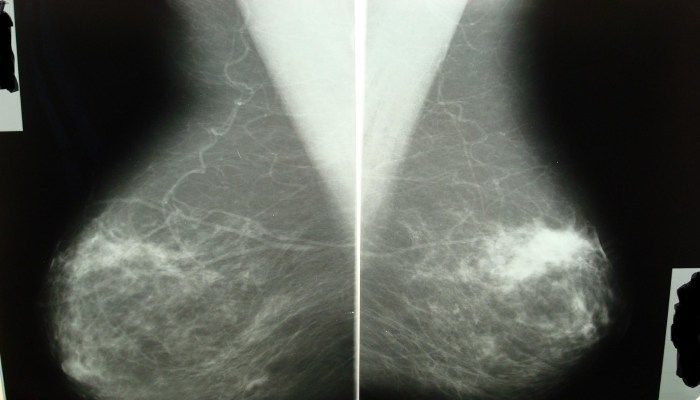

- Для подтверждения диагноза пациенту назначают маммографию — рентгеновское исследование груди. Маммография помогает определить размеры и форму образования. Обычно снимок делают в двух проекциях на второй неделе менструального цикла.

Диагностика узловой мастопатии включает в себя клинический осмотр, ультразвуковое исследование молочных желез и маммографию. В некоторых случаях может потребоваться биопсия для уточнения характера образований. Регулярные обследования у врача помогут выявить заболевание на ранних стадиях и предотвратить возможные осложнения.